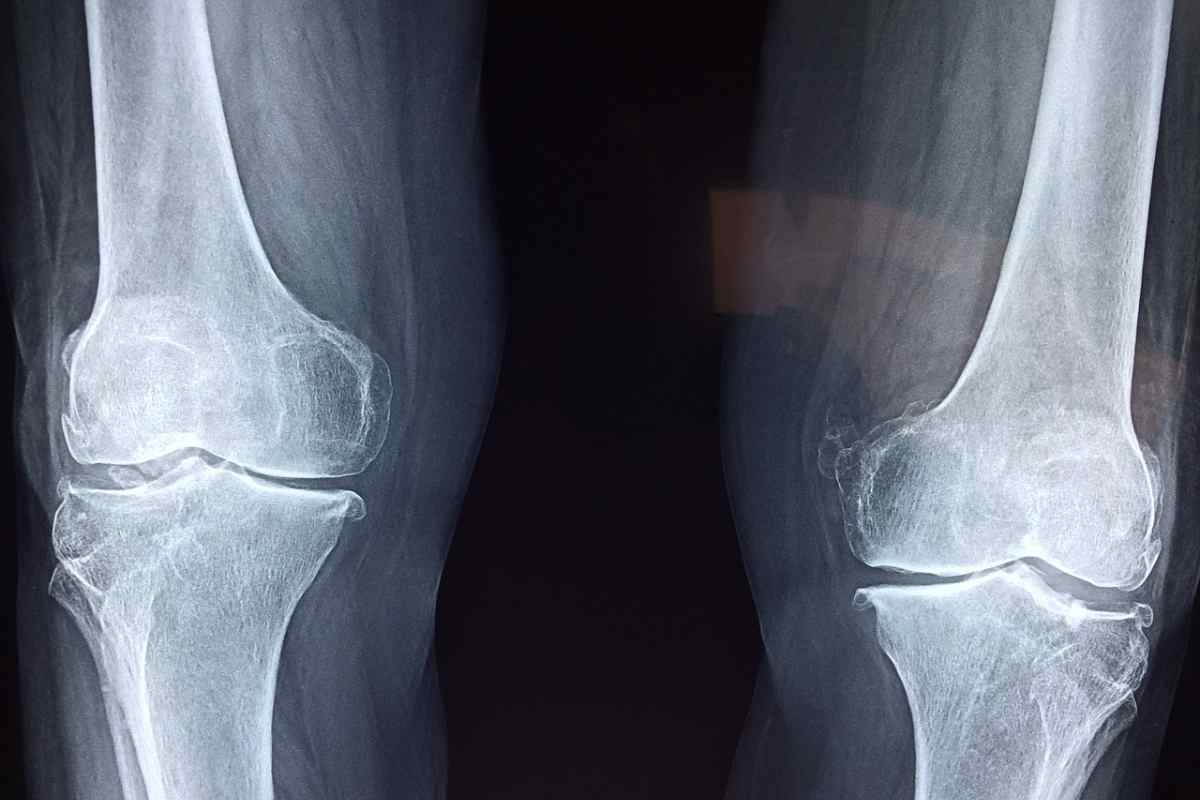

Si attendeva con grande apprensione il responso della risonanza magnetica per conoscere le reali condizioni dell’enfant prodige delle moto fuoristrada. Bollettino arrivato e pesantissimo per il pilota dell’Honda HRC: rottura del legamento crociato del ginocchio destro, con interessamento del menisco.

L’entità dell’infortunio è stata comunicata direttamente da Lawrence, sul proprio profilo Instagram in condivisione con quello del suo team: “Non è la notizia che tutti speravamo”, recita il messaggio allegato al video. Il classe 2003 di Landsborough si è operato martedì 4 febbraio e dovrà stare fuori per almeno quattro mesi.